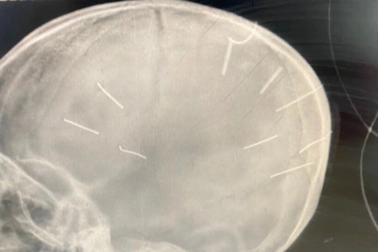

Xét xử vụ bé gái bị đóng đinh: VKS đề nghị điều tra vai trò người mẹTrong phiên tòa, nhiều câu hỏi, nghi vấn xoay quanh mẹ bé gái bị đóng đinh, về việc người phụ nữ này có biết những hành vi gây án của bị cáo hay không.

Ám ảnh "cha dượng" vụ bé gái bị đóng đinh và day dứt mang tên "mẹ ruột"Khi Nguyễn Trung Huyên, ác nhân đóng cả chục cái đinh vào đầu bé gái 3 tuổi đang bị đem ra xét xử thì ở Lâm Đồng, một người con riêng bị cha dượng bắn chết.

Từ vụ bé gái bị đóng đinh vào đầu: Cần trợ giúp khẩn cấp cho cha mẹ!Theo các chuyên gia, Covid-19 khiến tình trạng bạo hành trẻ em gia tăng với nhiều vụ việc ghê rợn, gần nhất là nghi án người tình của mẹ đóng đinh vào đầu bé gái 3 tuổi gây rúng động dư luận.